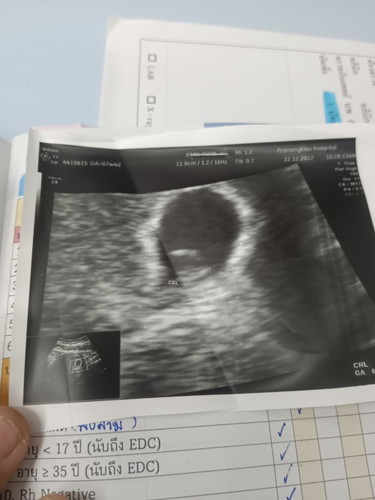

ภาพนี้ซาวด์ตอน6weeks อยากทราบว่าในภาพนี้มีเด็กหรือยังคะ

ของเค้าซาวตอน6wด้วยหมอบอกเจอถุงไข่แดง หัวใจเต้นปกติค่ะ